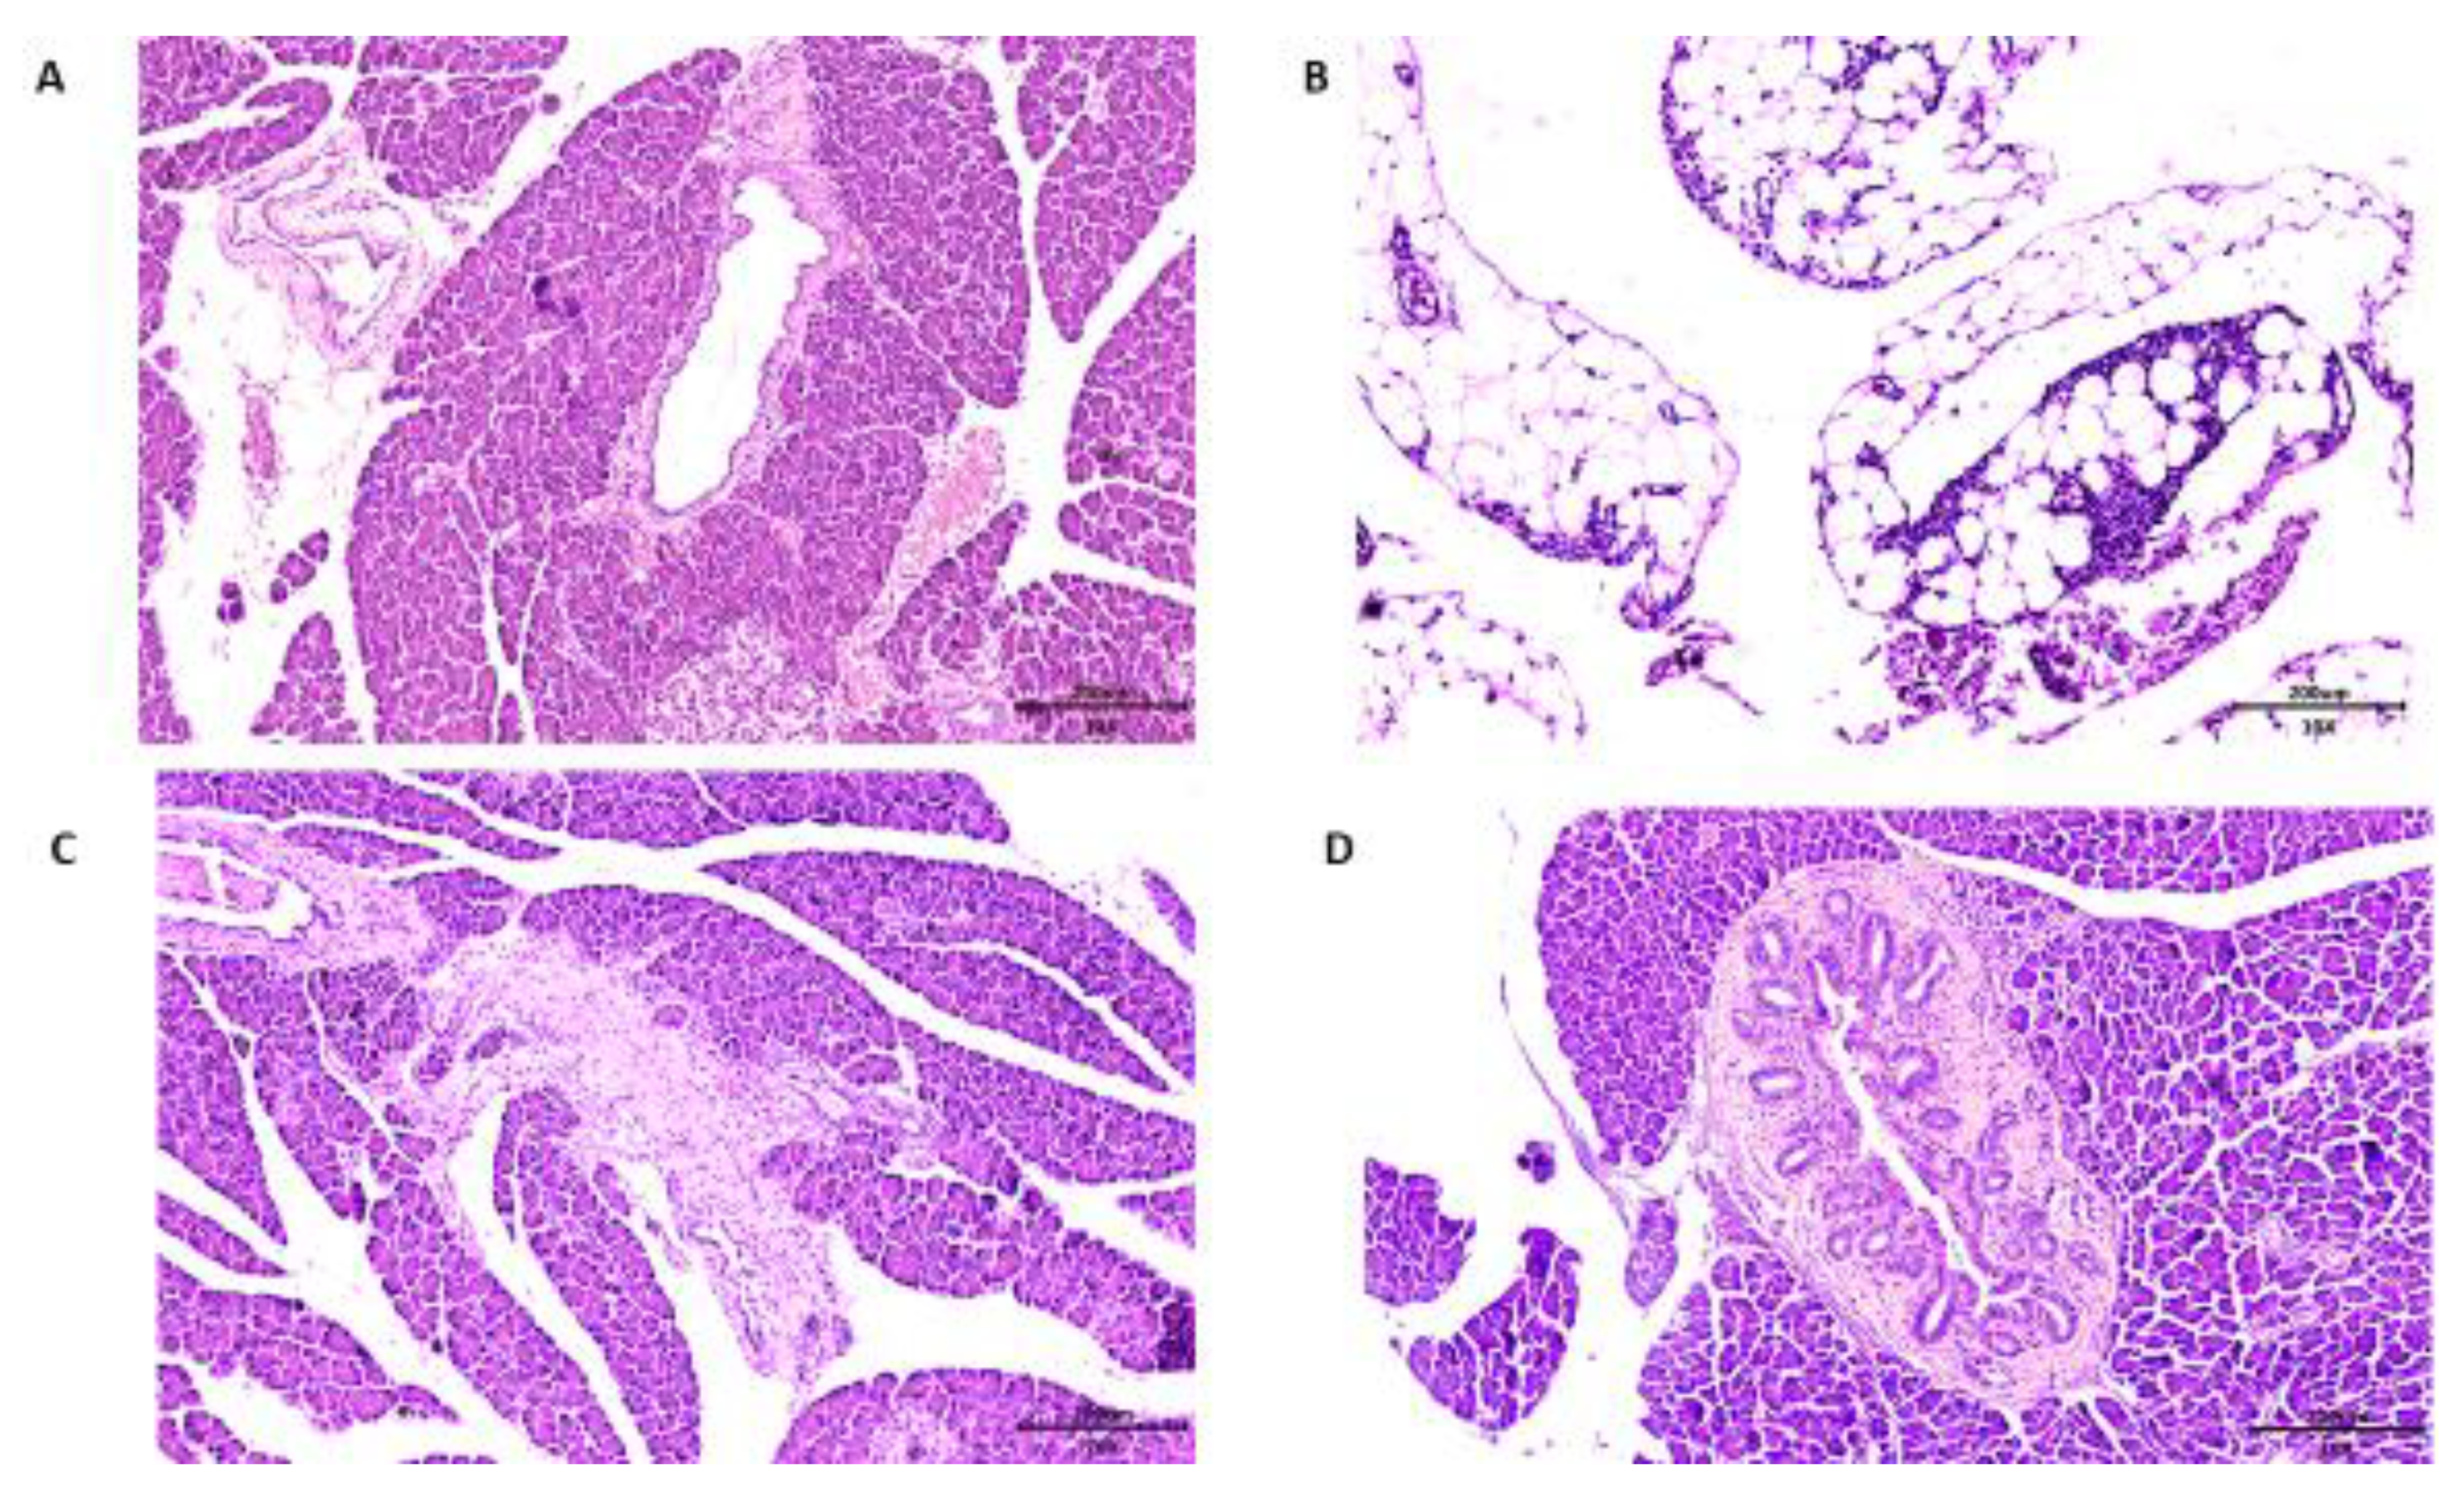

Concerning the histopathological analysis of the pancreas, Wistar rats of all groups presented chronic pancreatitis. In the group of rats that received no treatment, consuming only the HGLI diet, the main changes observed were related to hyperemia and acinar destruction, as well as the presentation of inflammatory, infiltrate in the pancreatic islet (Figure 7A). In the group that received the standard diet as treatment, the same conditions were presented. However, it was possible to observe a succinct replacement of adipose tissue, indicating an onset of tissue repair (Figure 7B).

Figure 7. Microscopy of the pancreas histopathology in Hematoxylin and Eosin (HE) staining, comparing the effect of different treatments on overfed rats. (A) The HGLI diet (high index and glycemic load), (20×/200 μm) induced hyperemia, scarce inflammatory infiltrate in septa, focal areas of acinar atrophy, and focal destruction of acini; (B) the standard diet (Labina®) (10×/200 μm) induced hyperemia, focal regions of exocrine glandular parenchyma reduction, and replacement of adipose tissue; (C) the HGLI diet + ECW (nanoparticles based on isolated tamarind trypsin inhibitor (TTI), purified chitosan and isolated whey protein (1:2:2 w/w/w)) (10×/200 μm) induced mild acinar atrophy, adipose tissue unilocular in the periphery of the gland with aspect of normality; (D) the HGLI + CW diet (nanoparticles based on purified chitosan and isolated whey protein (1:1 w/w)) (10×/200 μm) induced hyperemia, atrophy and acinar destruction, intralobular fibrosis, and morphological pancreatic duct evidencing the appearance of numerous mural ducts.

In the group that received ECW, the pancreas presented hyperemia, and a slight adipose tissue replacement in the exocrine glandular stroma parenchyma, with the presence of adipose tissue and a general aspect of normality, also suggesting an onset of tissue repair (Figure 7C). On the CW group, the pancreas presented a degenerative state, with pancreatic islet hyperplasia and morphological changes in the pancreatic ducts (Figure 7D).